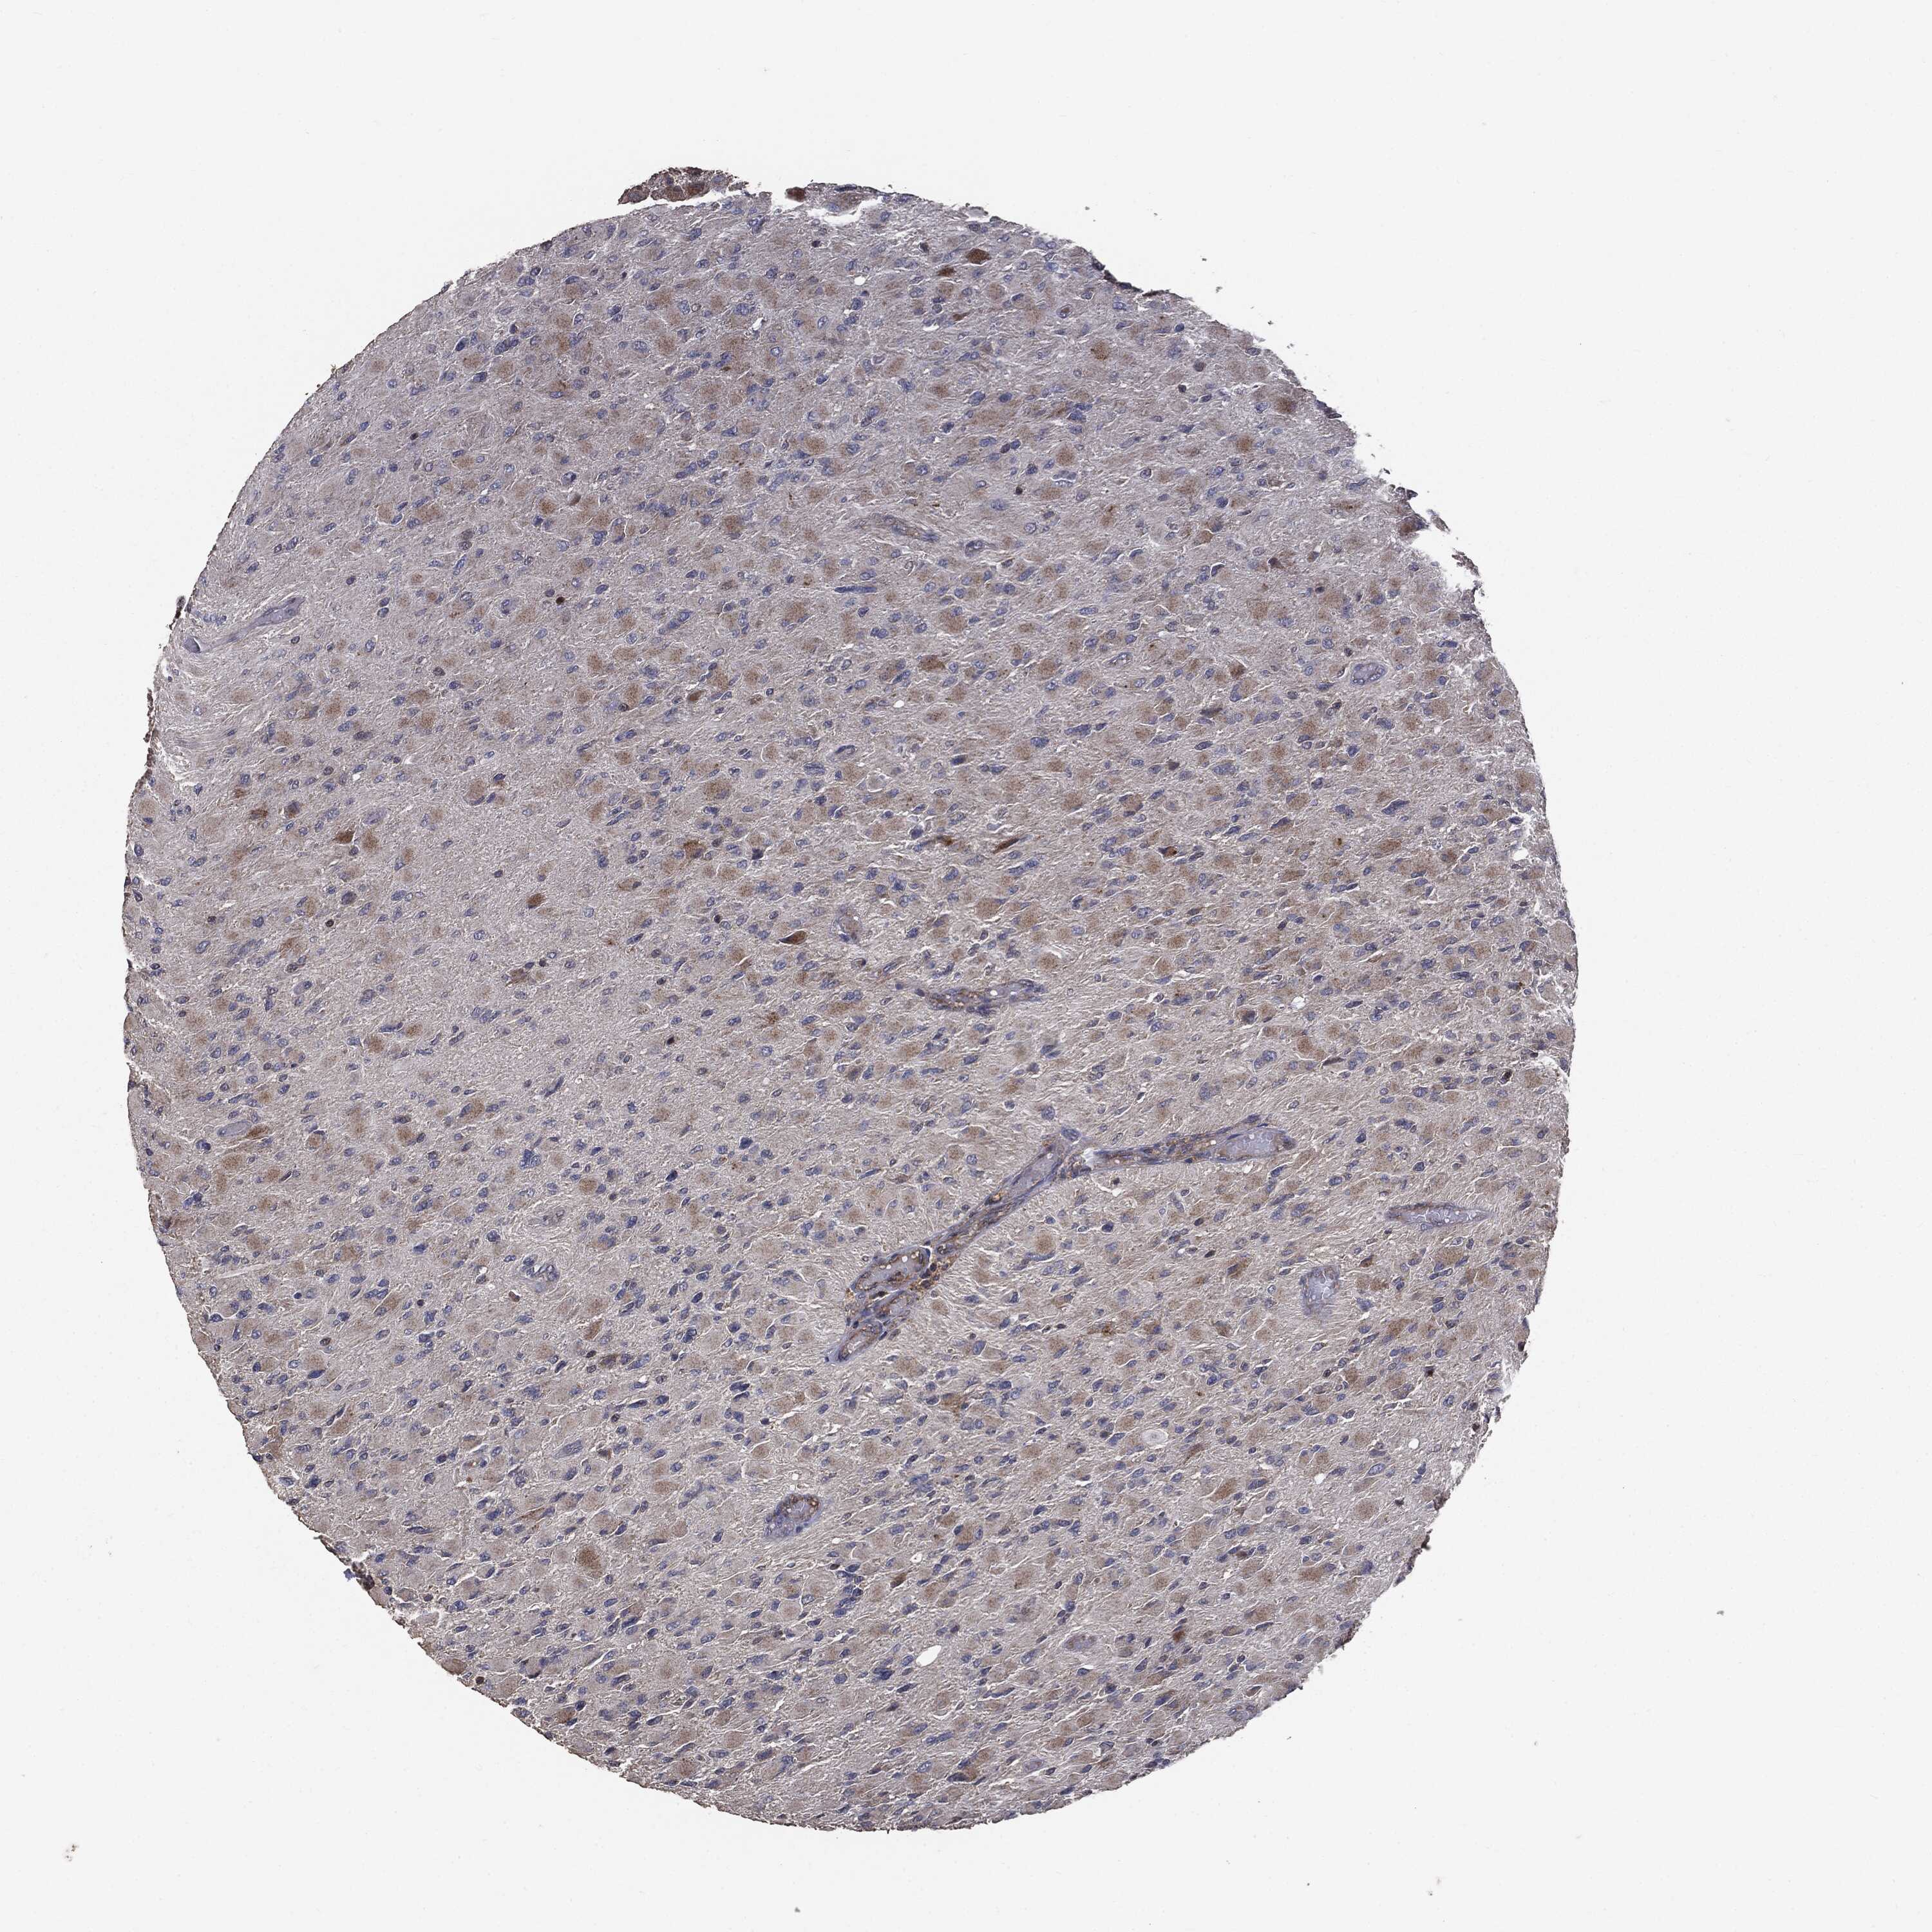

GLIOMA - Protein expressioni

A mouse-over function shows sample information and annotation data. Click on an image to view it in a full screen mode. Samples can be filtered based on level of antibody staining by selecting one or several of the following categories: high, medium, low and not detected. The assay and annotation is described here.

Note that samples used for immunohistochemistry by the Human Protein Atlas do not correspond to samples in the TCGA dataset.

Antibody stainingi

Antibody staining in the annotated cell types in the current human tissue is reported as not detected, low, medium, or high, based on conventional immunohistochemistry profiling in selected tissues. This score is based on the combination of the staining intensity and fraction of stained cells.

Each image is clickable and will lead to virtual microscopy that enables deeper exploration of all samples and also displays staining intensity scores, fraction scores and subcellular localization as well as patient and tissue information for each sample.

CAB069425

CAB080053

CAB080065

CAB080070

CAB080081

CAB080095

CAB080097

Staining

High

Medium

Low

Not detected

Intensity

Strong

Moderate

Weak

Negative

Quantity

>75%

75%-25%

<25%

None

Location

Nuclear

Cytoplasmic/membranous

Cytoplasmic/membranous,nuclear

Glioma, malignant, Low grade

Glioma, malignant, High grade

Glioma, malignant, NOS